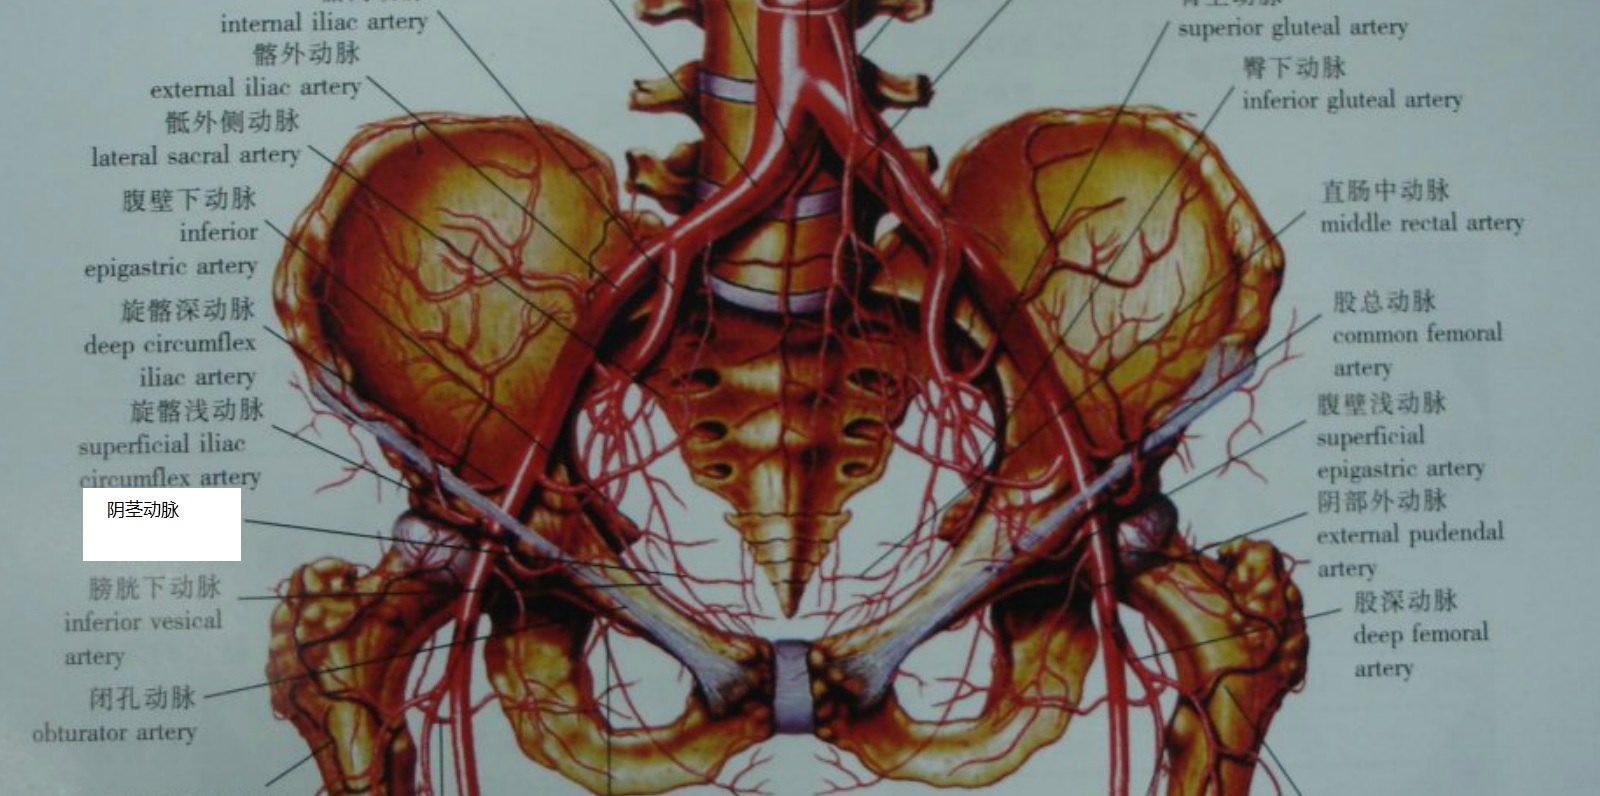

盆腔血管部分分支_动脉

图片尺寸1000x750